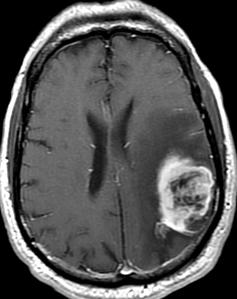

Tumor cerebral: condición que puede afectar funciones ... 😈

¿Cuántos tipos de tumores cerebrales hay? | Confirmado 😈

Tumor cerebral, ¿qué es y cuando ir al médico ... 😈